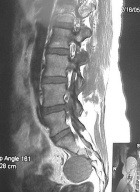

50 year old woman with a two year history of low back pain

Zoom image: Radiological image Radiological image.